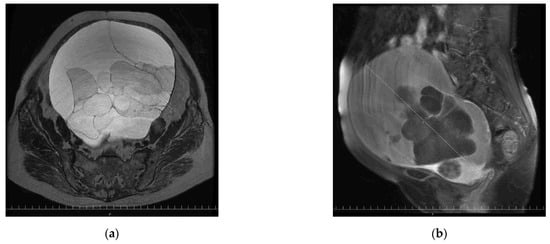

2. Case Presentation Section